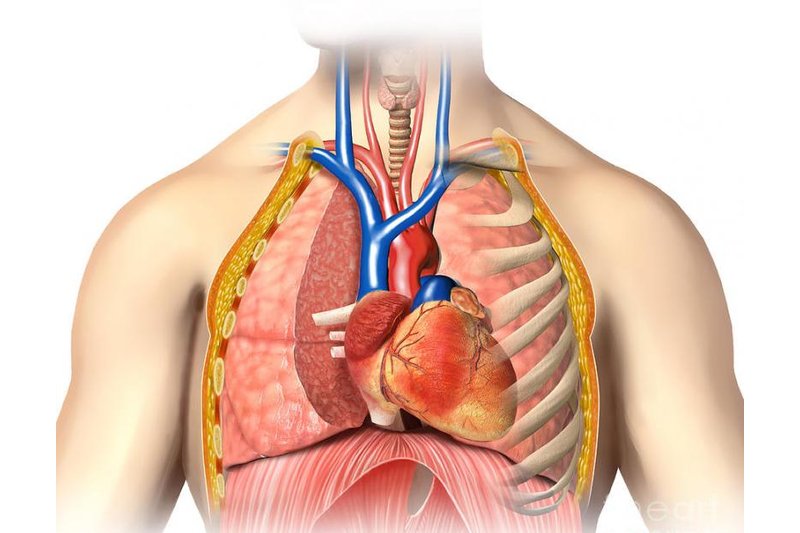

Анатомия Сердца: Расположение и Функции